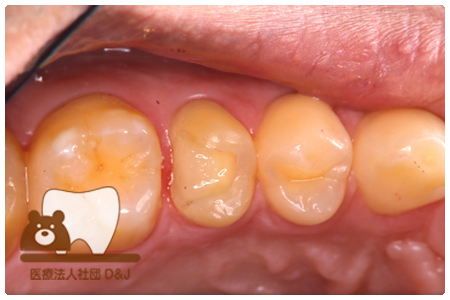

症例4フルジルコニアクラウン 左下6

治療前

治療後

37歳 男性

- 治療内容

- 以前のクラウンがセメントの劣化により外れた為その上にフルジルコニア製の被せ物を装着しました。見た目と強度を両立した自由診療の治療です。

- 治療期間

- 1カ月

- 費用

- 自費

フルジルコニアクラウン:77,000円(税込)

(R8.1月時点)

- その他の治療の費用は含まれておりません。

- リスク・副作用

- 硬い素材のため、かみ合う歯に負担がかかることがあります。将来取り外す場合に歯に負担がかかることがあります。強い力が加わると、まれに欠けたり割れたりすることがあります。